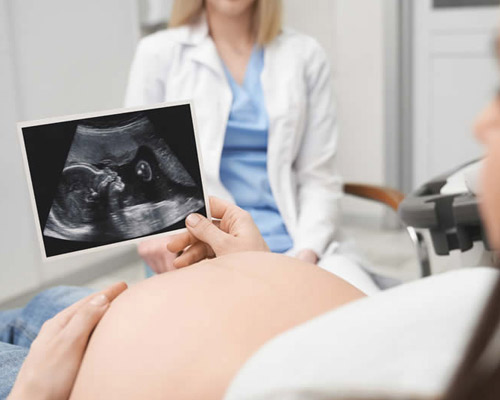

First, a small amount of ultrasound gel is applied to the abdomen. This gel allows the ultrasound probe to move smoothly across the skin and improves the quality of the images.

The sonographer then gently moves the ultrasound probe over the abdomen. The probe sends sound waves into the body, and the returning echoes create images of the baby on the screen during your pregnancy scan at the Sheffield appointment.

You will be able to see your baby’s movements, heartbeat, and position during the scan.

During the scan, a sonographer applies ultrasound gel to your abdomen and moves a small probe across the skin to create images of your baby. You will be able to see your baby on the screen while the sonographer explains what is visible during your pregnancy scan at the Sheffield appointment.